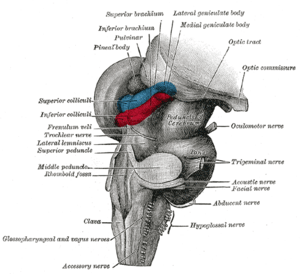

Anteroinferior view of the medulla oblongata and pons | |

Axial section of the pons, at its upper part Hind- and mid-brains; posterolateral view

Hind- and mid-brains; posterolateral view Median sagittal section of brain